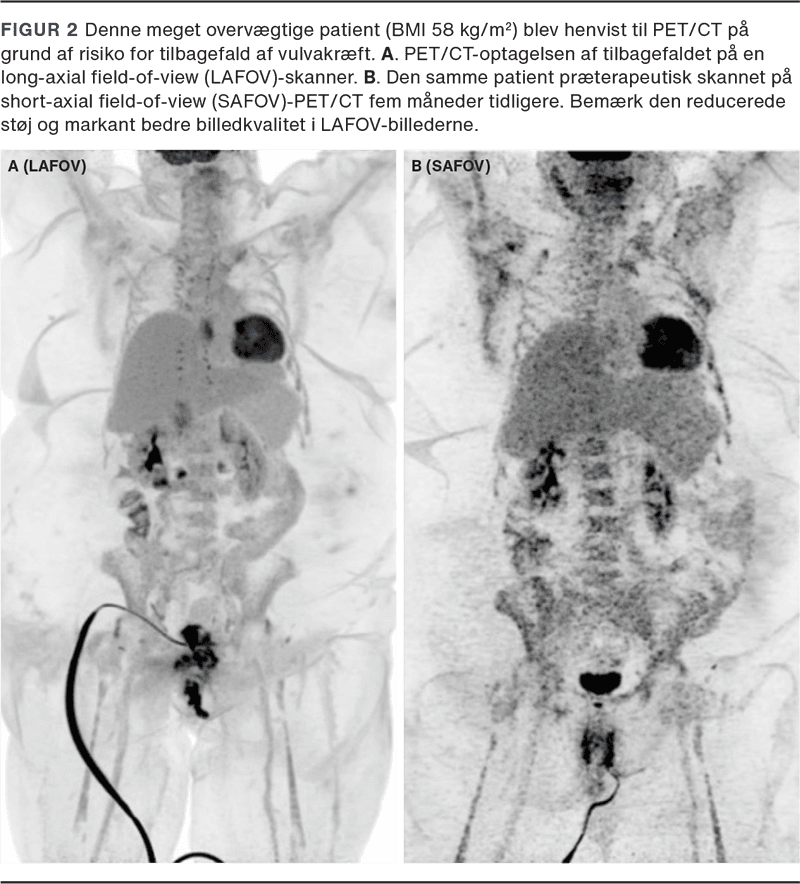

Fordelene ved LAFOV-PET/CT er særlig tydelige i pædiatrien og hos overvægtige. Hos pædiatriske patienter betyder de meget korte skanningstider, at undersøgelser ofte kan gennemføres uden sedation eller anæstesi samtidig med, at en lav stråledosis fastholdes. Dette har stor betydning hos spædbørn og små børn og har bidraget til en bredere anvendelse af PET/CT i denne patientgruppe [3]. Hos overvægtige patienter bliver en stor del af fotonerne absorberet i kroppen, men den højere følsomhed i LAFOV-skannere giver markant bedre billedkvalitet og tillader kortere skanningstid (Figur 2).